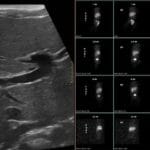

- Radiology Cases: Images with a to-the-point discussion highlighting the specific diagnostic criteria.

- Radiology Case of the Day Collection: Aunt-Minnie Board Cases for Rapid Review.

- Radiology Spotters: 700+ spot / “Aunt-Minnie” cases divided into sets of 10 each!